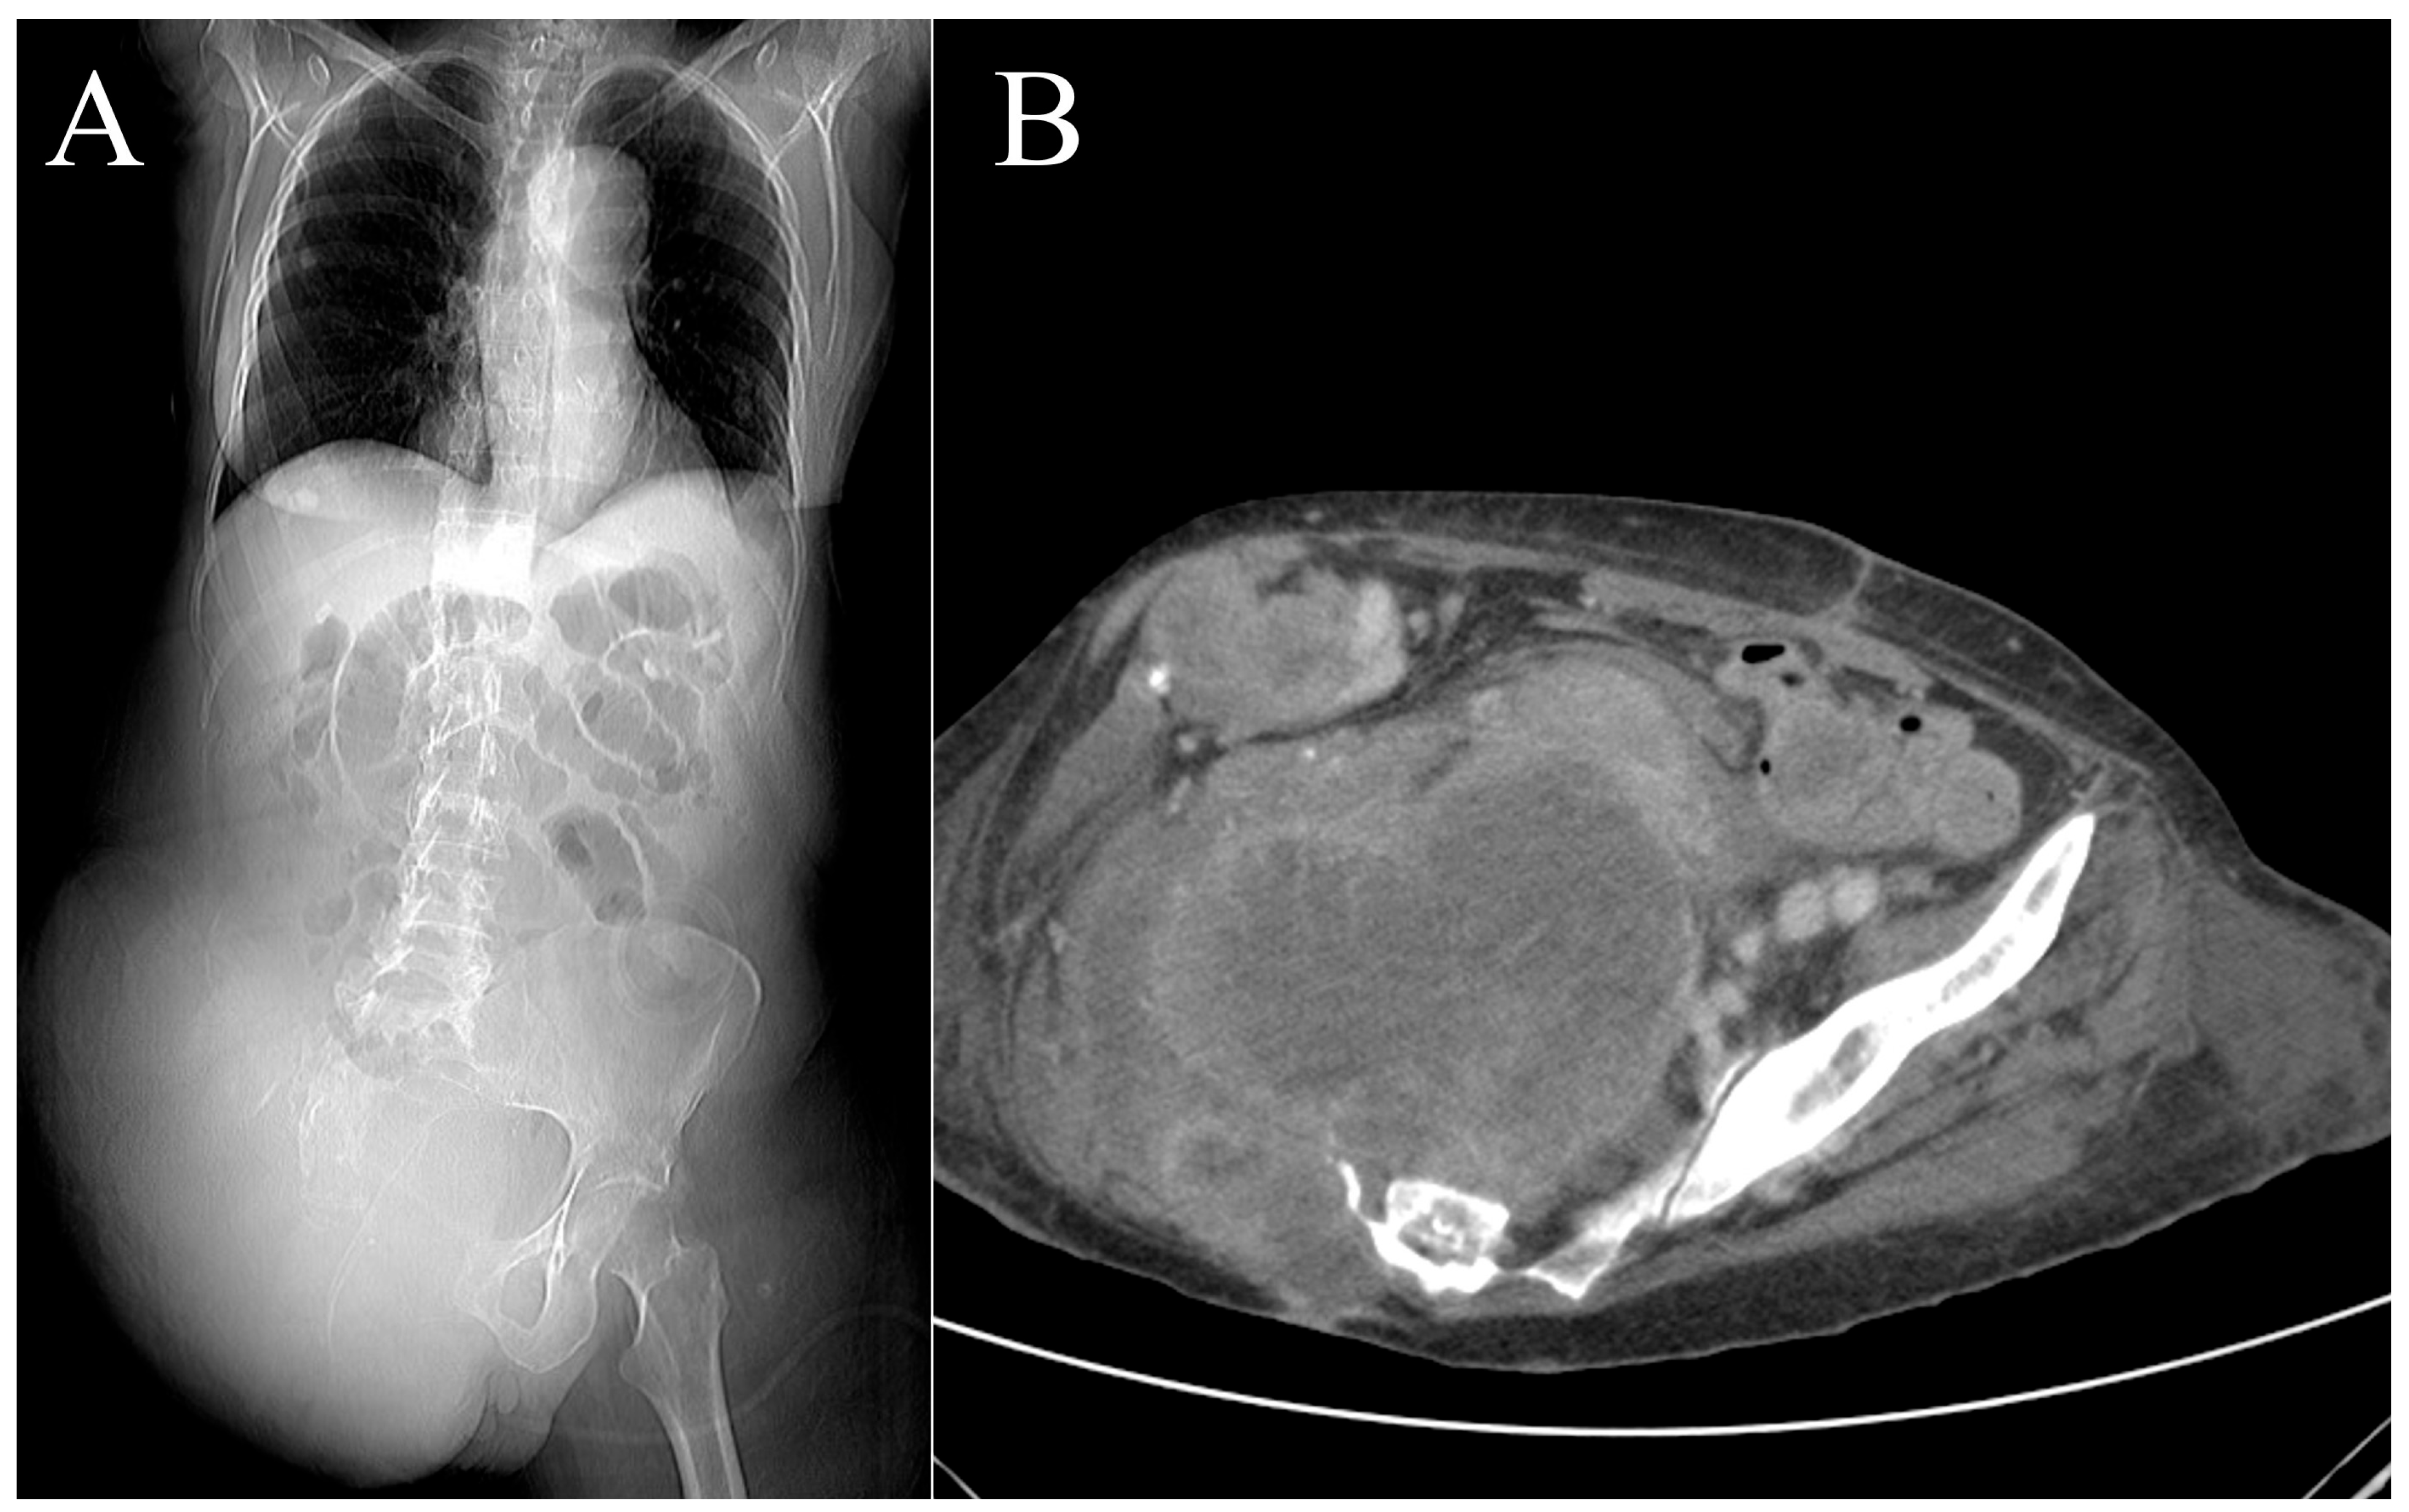

2.2. Case 2

3.2. Case 2